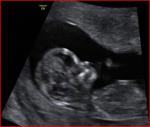

read a study published in BBC website saying that

female babies have more HCG ( human chorionic gonadotropin) that is

the hormone produced during pregnancy than male babies .

As we know home pregnancy test depend on this hormone to show you

the result (positive or negative) .